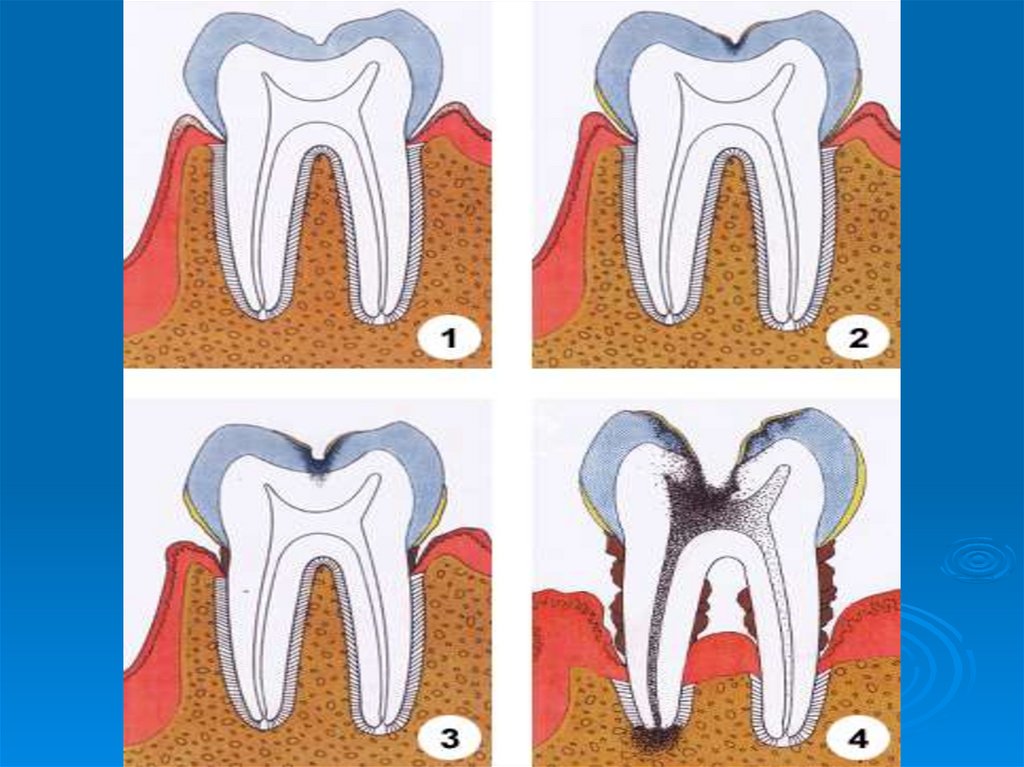

Кариес зубов – патологический процесс, проявляющийся после прорезывания зубов, при котором происходят деминерализация и

Современная концепция этиологии кариеса

6. Кариес зубов – патологический процесс, проявляющийся после прорезывания зубов, при котором происходят деминерализация и

размягчение твердых тканей зуба с

последующим образованием

дефекта в виде полости.

Кариес – это моноэтиологическое и

полифакторное заболевание